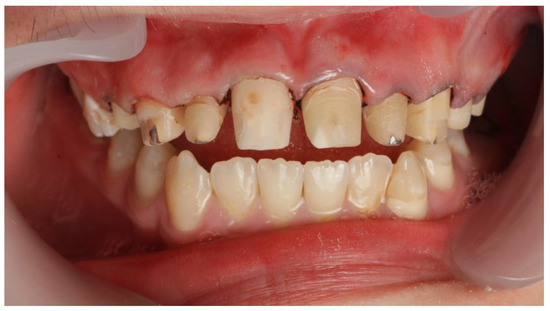

2. Case Report